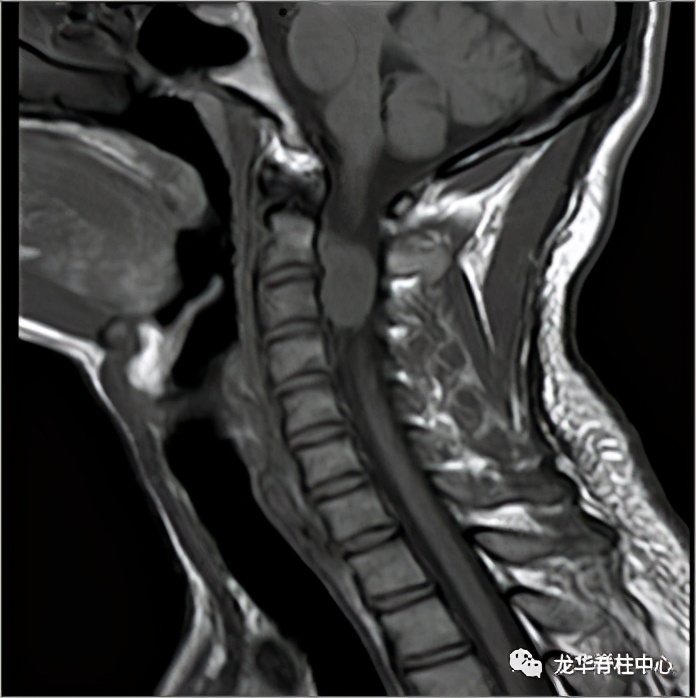

显微镜下寰枢椎脱位经口松解、后路固定术

开展深圳市首例寰枢椎脱位经口咽松解、后路椎弓根钉板内固定术